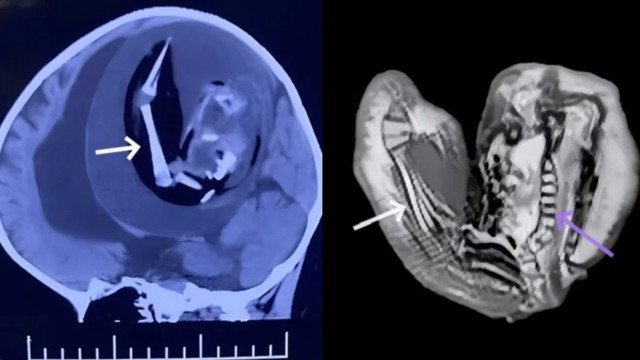

A menina, que não apresentava nenhum atraso no desenvolvimento até o nascimento, começou a ter dificuldades para aprender a andar, sentar e falar. Além disso, sua cabeça era um pouco maior do que o esperado para crianças da sua idade. Preocupados, os pais da bebê procuraram ajuda médica. Uma tomografia computadorizada revelou um tumor de grandes proporções no crânio da criança.

A equipe médica decidiu realizar uma cirurgia para remover o tumor. Durante o procedimento, os cirurgiões descobriram que a massa era, na verdade, um feto encapsulado, um irmão gêmeo da menina que não se desenvolveu completamente no útero e ficou preso em seu crânio.

Na região ao redor da cápsula, também foram descobertos vários tumores. Toda a massa comprimia o cérebro da bebê, o que causou um quadro de hipertensão craniana. Apesar dos esforços médicos, durante a operação a criança ficou inconsciente após o procedimento e teve convulsões. Infelizmente, ela não resistiu e faleceu 12 dias depois.